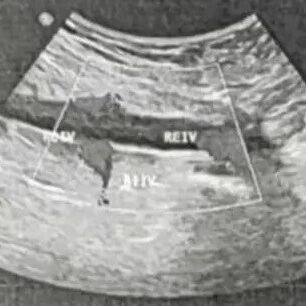

复发性静脉血栓形成原因待查:白塞病?一例报告及诊疗思路分析